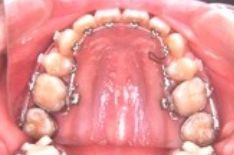

* 歯の裏側に付ける為、装置が見えない

* 歯みがきが難しい

* 治療当初、舌への違和感がある

* 1回の治療時間が表に比べて長い

大人の方で、仕事の都合でどうしても表側につけられない患者さん向けの方法です。